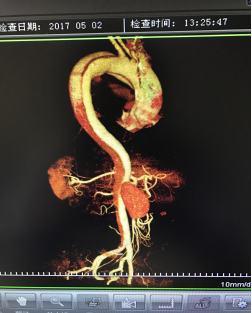

5月2號劉大伯照常早起干活,突然胸部劇烈疼痛,難以忍受,全身大汗,同時伴有右上肢發(fā)涼,他心想這次心絞痛比之前嚴(yán)重的多啊,趕緊叫上孩子到吉林國文醫(yī)院心血管內(nèi)科住院,患者長期高血壓病史,血壓一直控制不理想,大夫給他做了檢查,測左上肢血壓:82/45mmHg,右上肢血壓測不出,心率52次/分,右側(cè)肱動脈、尺動脈、橈動脈搏動消失,左側(cè)股動脈搏動較右側(cè)弱?!霸懔耍p側(cè)血壓差別這么大,是不是主動脈夾層了?”,接診大夫趕緊找來李主任,李主任反復(fù)詢問患者病情,表情突然凝重起來,患者胸痛這么明顯,血壓低的厲害,主動脈夾層的可能性很大。二話不說,李主任立即聯(lián)系影像科的醫(yī)生準(zhǔn)備做主動脈CTA,移動患者做檢查的過程大夫們非常小心,嚴(yán)密監(jiān)測患者血壓變化情況。兩個小時后結(jié)果出來了,主動脈夾層從升主動脈一直撕裂到左側(cè)髂總動脈?。?!

李主任詳細(xì)的與劉大伯的女兒交代了病情,手術(shù)是挽救生命的唯一辦法,為了劉大伯的一線生機(jī),我們積極聯(lián)系了我省權(quán)威的心血管外科,并做了詳細(xì)的匯報,兩家醫(yī)院對此非常重視,為劉大伯開通了綠色通道,安全的把他總到上級醫(yī)院,當(dāng)天便給他進(jìn)行血管置換及覆膜支架植術(shù)。他術(shù)后恢復(fù)的很好,后來劉大伯的女兒看望我們,感嘆道:沒想到國文醫(yī)院心內(nèi)科應(yīng)急能力這么高,在那么短的時間內(nèi)診斷明確,才給了我的老父親手術(shù)的機(jī)會。